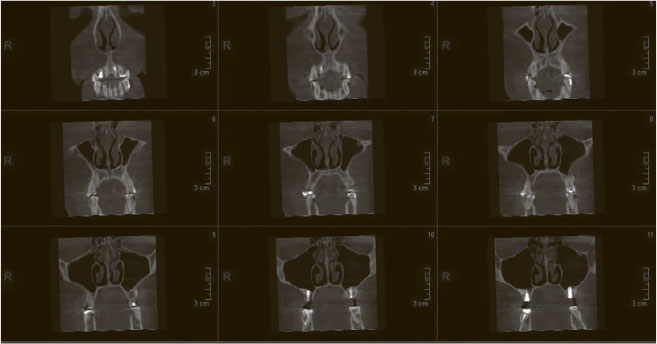

Компьютерная томограмма придаточных пазух носа, фронтальная проекция

Был у Скотиныча случай, когда мама юного пациента с обычным насморком осталась крайне недовольна консультацией, ибо считала, что у ребенка большая беда (последний в тот момент наворачивал круги по кабинету и хохотал, аки герой мультфильмов Текса Эйвери[2]). На прием чадо привел отец, что тоже стало отягчающим обстоятельством. Отправились они к другому доктору, и тот, потирая потные ладошки, назначил КТ, на которой оказалось, что по всем пазухам у пациента небольшие отеки (такая томограмма будет у любого ребенка с насморком). Доктор поцокал языком, вынес вердикт, что бедолаге осталось недолго, и принялся активно его лечить списком из восьми препаратов и, само собой, платными процедурами. Естественно, Скотинычу выставили счет за все это дело, однако независимые эксперты с нашей благословенной кафедры на досудебном этапе поддержали тактику Скотиныча. Мама, безусловно, осталась злой и недовольной, но это уже другая история.